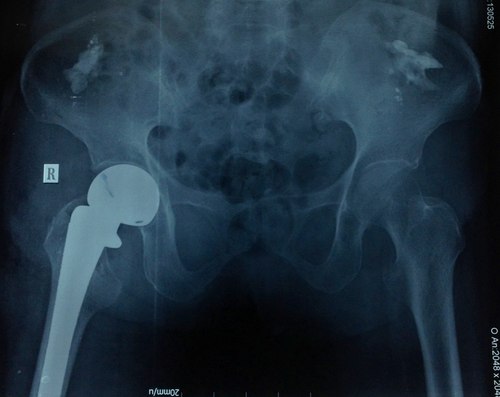

Cụ bà 93 tuổi, ngụ quận 7, TP HCM vừa được các bác sĩ Bệnh viện Nhân dân 115 phẫu thuật thay khớp háng chuôi dài sau khi té ngã trượt chân trong nhà tắm.

Theo tiến sĩ Nguyễn Đình Phú, Phó giám đốc Bệnh viện Nhân dân 115, bệnh nhân được chuyển đến bệnh viện vào ngày 21/5 trong tình trạng đau ngất và không cử động được chân bên phải sau khi sơ ý té trượt chân trong nhà tắm do nền gạch trơn.

Hình ảnh phim chụp khớp háng bệnh nhân 93 tuổi. Ảnh: T. Đ.P

Bác sĩ Phú cho biết, bệnh nhân được nhanh chóng phẫu thuật thay khớp háng chuôi dài thế hệ mới. Đây là loại khớp háng mới được ứng dụng cho các loại gãy cổ xương đùi phức tạp có đường gãy lan xuống dưới làm mất vững. Sau hậu phẫu 7 ngày, bệnh nhân đã vận động nhẹ tại giường chân phải và bớt đau đớn. Khả năng sau 3 ngày nữa là bệnh nhân có thể xuất viện.

Bác sĩ Phú cũng cho biết thêm, trước đây những bệnh nhân già yếu, lớn tuổi thường ít được can thiệp phẫu thuật. Do các nguy cơ tim mạch thường làm bệnh nhân tử vong trên bàn mổ rất nhiều nên các bác sĩ thường e ngại phẫu thuật và thường dùng phương pháp điều trị bảo tồn. Hiện nay, các bác sĩ khoa chấn thương chỉnh hình tại bệnh viện phối hợp với khoa gây mê hồi sức, các khoa tim mạch …đã giải quyết thay khớp háng cho nhiều bệnh nhân già yếu bị gãy cổ xương đùi.